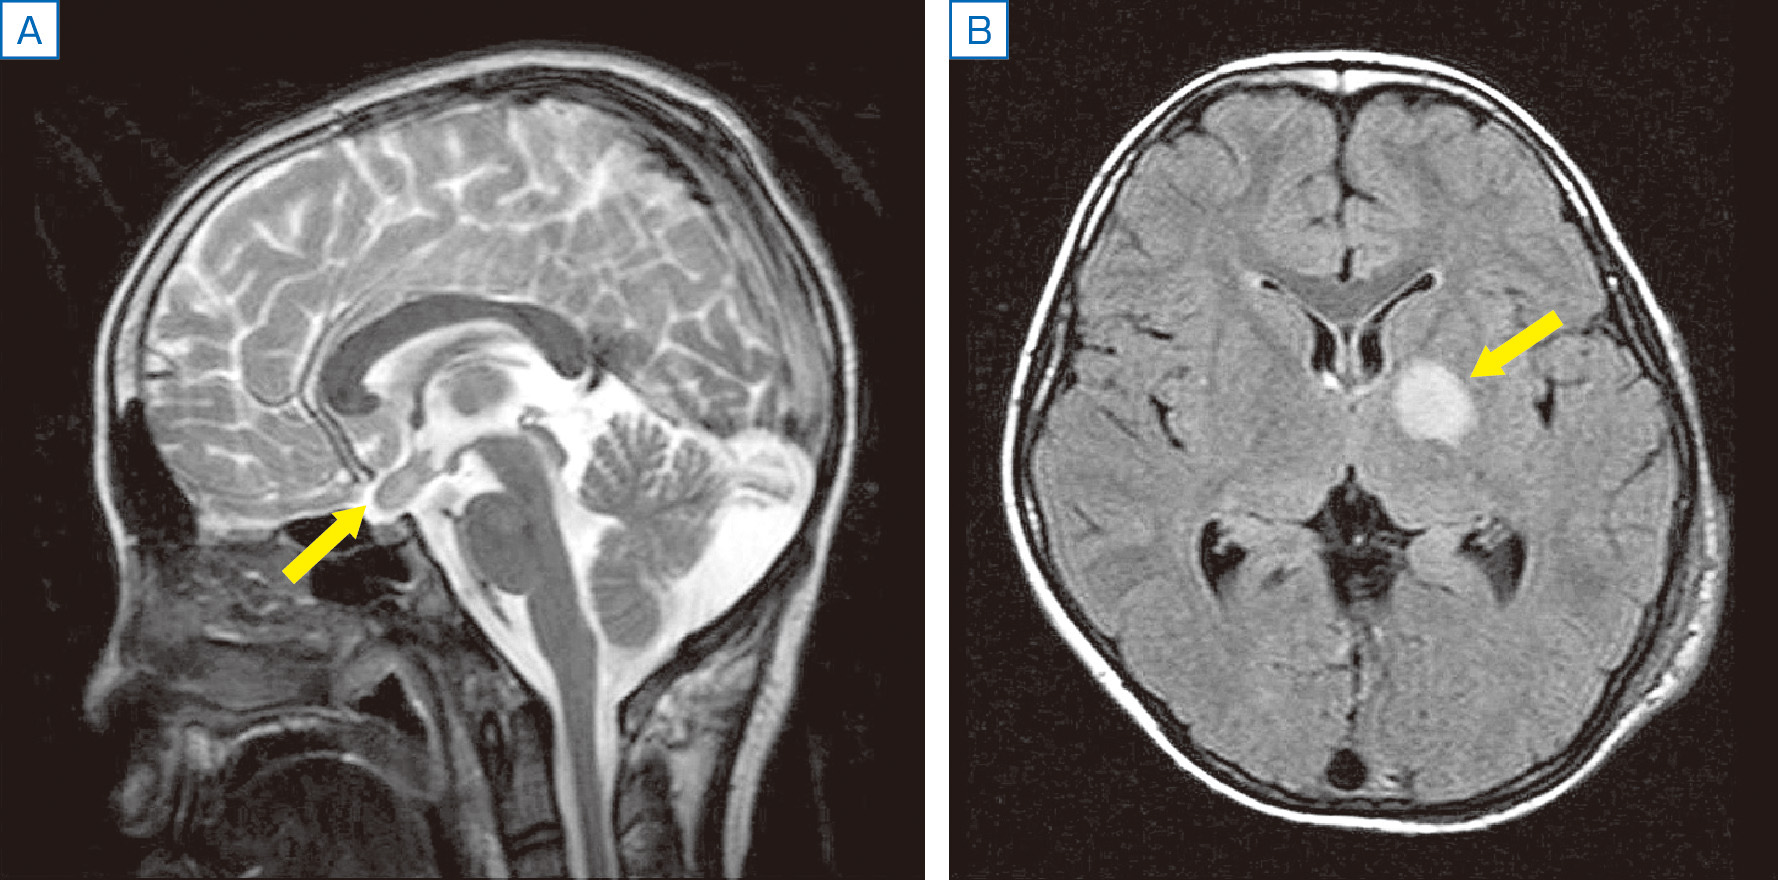

交通事故医学の基礎等-交通事故-小松亀一法律事務所。NEW!頭頸部の矢状断面 | 京都科学。C12.jpg?resize=150,150&ssl=1。晒よし飴 35g。※簡易的な額をおつけしますので、到着後すぐに飾れます。黒のインクで精密に描写された骨格と神経に、赤いラインが脳の血管を際立たせる。【Dalle】医学部失敗(2014〜2015)防衛大退校(2016)ひきこもり(2017〜2018)Fラン大中退(2019〜2022)自動車学校中退医学部再受験(2021/8/7~)地方国立医大合格(2023) 【画材】絵画の種類···その他形式···その他主題···その他主な画材···マジックペン、ケント紙大きさ…A4(キーワード)帆船、イラスト、マジックペン、苦学生、絵画、デッサン、芸術、美術、船、自衛隊、海上自衛隊、海上保安庁、医学部、医学、学生、験担ぎ、受験、合格、鯨、マンタ、牛、猫。頭部断面モデル,正中矢状断,前額断 | 日本スリービー。繊細なペン画で描かれた頭部の断面図。【古塔つみ/COTOH TSUMI】ユニーク作品。カントク ハニカムアートフレーム キャンバスアート まとめ売り。医学的な正確性とアートの美しさが見事に調和した一枚。鶴田一郎 リトグラフ「メモリアルブーケ」美人画 和風 女性肖像画 フレーム付き